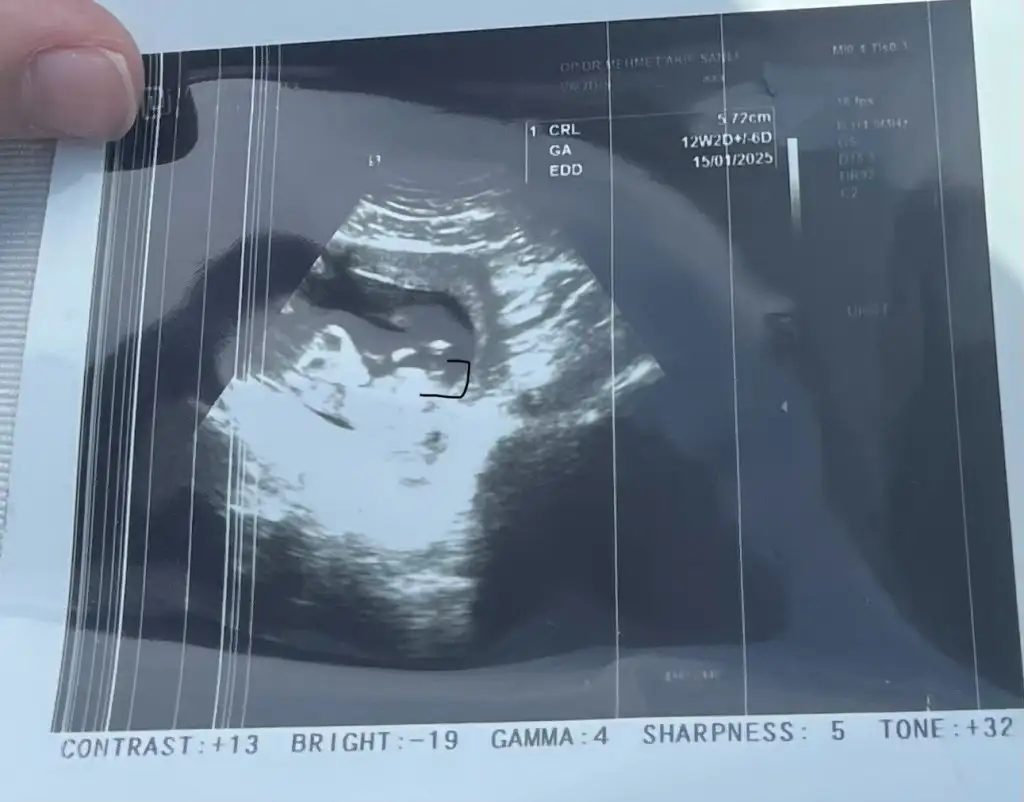

Nub teorisiyle bebiş cinsiyeti belli olur mu, bilginiz var mı, ne kadar güvenilir acaba

Doktor erken ama tahmin edeyim dedi %80 erkek dedi sonra,(12+2 ) ‘ yken baktı bu arada.

Ancak teoriye göre kız gibi duruyor sanki, o gözüken çıkıntı pipiş oldaydı net erkek derdi öyle değil mi?